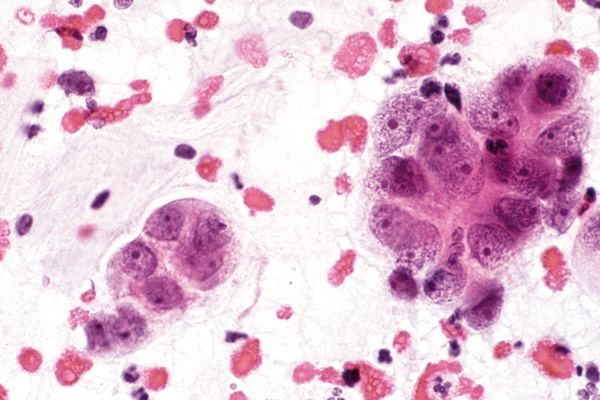

Juni

richtige Antwort:

a. Zellen eines Ovarialkarzinoms

- unregelmäßiges, vergröbertes Chromatin der Zellkerne

- Vakuolisierung des Zellplasmas

- häufige Lagerung in Haufen oder größeren Gruppen

- Psammonkörperchen können fehlen und sind kein Hinweis auf Malignität

- Adenopapilläre Struktur der Tumorzellen